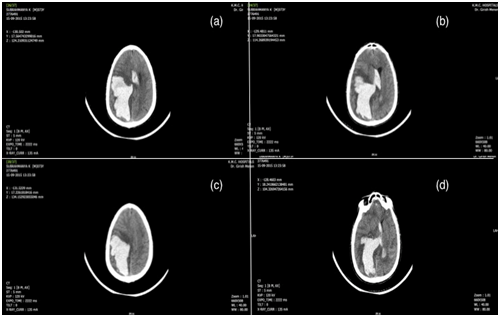

A 73-year-old diabetic, hypertensive male presented with the history of sudden onset altered sensorium and left sided weakness. On admission, nearly 4 hours after the ictus, he was intubated and had a Glasgow Coma Scale (GCS) of E1M3 with pupillary asymmetry, right pupil being larger. His blood pressure was high on admission (200/120mm of Hg) and his blood sugars were 236gm%. His Computed tomographic scan of the (CT) brain showed a massive right-sided parieto-occipital bleed with intraventricular extension and early hydrocephalus along with diffuse oedema (Figure 1). (SICH score 5). After explaining the pros and cons of intervention, he was taken up for evacuation of the haematoma under GA. As the brain remained full even after clot evacuation the bone flap was not replaced and a lax duroplasty was done. Preoperatively he remained stable with no major hemodynamic fluctuations. His blood pressures were maintained around a MAP of 100-120 mm of Hg as is the unit protocol. He was electively ventilated and started on decongestants. Postoperative CT scan done on day1 showed a large right ICA infarct with mass effect and midline shift (Figure 2). Thereafter he continued to deteriorate in spite of full cerebral protective measures and eventually succumbed 3 days after surgery.

Figure 2 Postoperative axial CT Scans showing a large right ICA infarct with mass effect and midline shift with effacement of basal cisterns and significant cerebral oedema (a to d).